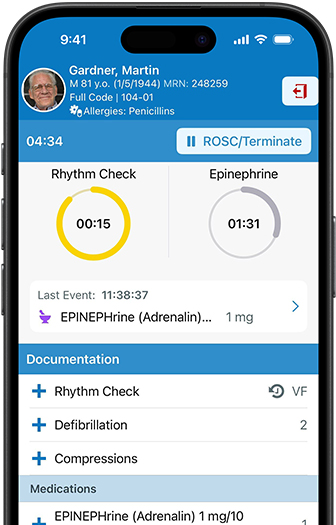

Apple devices unlock new levels of mobility, efficiency, and collaboration for clinicians. Care teams can treat patients on the fly and zip through demanding workloads with ease. When providers have the freedom and time to work on their own terms, they can focus on what really matters — their patients.

Epic Hyperspace helps providers access and update patient records quickly and easily. Authenticate using Touch ID and stay a step ahead with AI-powered clinical summaries, AI-drafted replies to patient messages, and ambient documentation technology.

Epic Haiku and Limerick on iPhone and Apple Watch give authorized clinicians secure access to patient records from iPhone. Real-time updates and notifications can be displayed on iPhone and Apple Watch with Epic Limerick.

Epic Rover for iPhone offers nurses seamless communication and documentation tools.